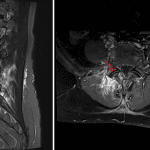

- T2/STIR hyperintense signal and enhancement in the right L4-L5 facet joint extending into the adjacent articular pillars and L4 and L5 pedicles

- T2/STIR hyperintense signal and enhancement in the surrounding right posterior paraspinal soft tissues and musculature without peripherally enhancing collection

- T2/STIR hyperintense signal and enhancement in the anterior aspects of the L2 inferior endplate and L3 superior endplate without intervening disc signal abnormality

- Septic facet arthritis

Findings consistent with septic arthritis involving the right L4-L5 facet joint with associated osteomyelitis involving the adjacent articular pillars and L4 and L5 pedicles. No epidural abscess or significant associated spinal canal or neural foraminal compromise.

Adjacent myositis without soft tissue abscess.

T2/STIR hyperintense signal and enhancement in the anterior aspects of the L2 inferior endplate and L3 superior endplate, which is favored degenerative in etiology given lack of abnormal disc signal. Recommend attention on followup imaging.